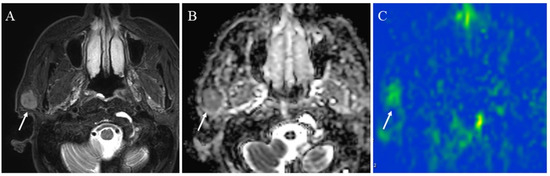

5.1.2. Hypervascular Lesions

- van den Berg, R. Imaging and management of head and neck paragangliomas. Eur. Radiol. 2005, 15, 1310–1318. [Google Scholar] [CrossRef] [PubMed]

- Alimli, A.G.; Ucar, M.; Oztunali, C.; Akkan, K.; Boyunaga, O.; Damar, C.; Derinkuyu, B.; Tokgöz, N. Juvenile Nasopharyngeal Angiofibroma: Magnetic Resonance Imaging Findings. J. Belg. Soc. Radiol. 2016, 100, 63. [Google Scholar] [CrossRef]